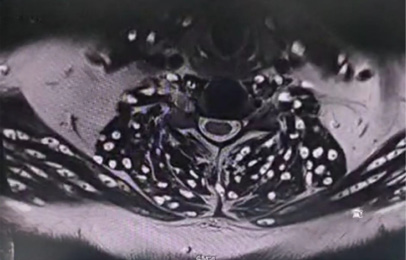

Spinal MRI revealed reversal of cervical lordosis with diffuse disc bulges at levels C3/4, C4/5, C5/6, and C6/7, causing mild anterior thecal-sac indentation but without evidence of cord compression or myelomalacia (Figures 4–7) [5]. The lumbar spine showed disc desiccation with a diffuse bulge at L4–L5, indenting the thecal sac yet preserving normal vertebral body height and marrow signal intensity. No paravertebral abscess, vertebral destruction, or compressive myelopathy was noted [6].

Explanation: Imaging showed diffuse disc bulges at multiple cervical levels (C3–C7) and at the lumbar level (L4–L5). These changes caused indentation of the anterior thecal sac, consistent with early degenerative disc disease. Although unrelated to the parasitic infection, these findings explained the patient’s chronic pain and required attention to avoid future complications.